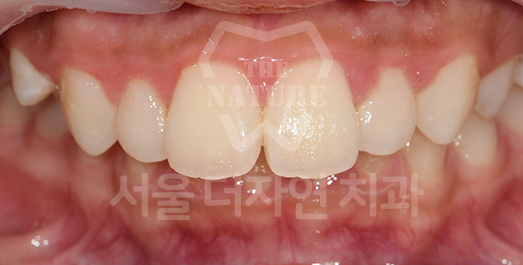

Diastema (Spacing) Solution

We first diagnose whether the spacing is generalized throughout the dentition

or localized to specific areas such as the anterior teeth.

Treatment involves attaching orthodontic appliances and

moving the teeth into the vacant spaces to achieve proper alignment.

BEFORE: 2020.11.12

AFTER: 2023.04.06